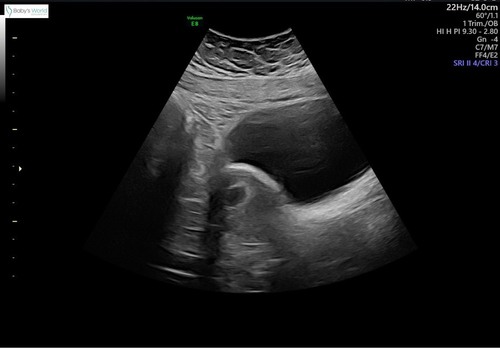

Nou dit is dus precies bij mij gebeurt! Ze liep ook nog eens uit dus ik hopte door de wachtkamer hahaha. Zodra ze begon met de echo zei ze ook meteen, ga maar plassen, de zwangerschap zit op de goede plek, maar je blaas is veels te vol! Zie foto, hahahha!